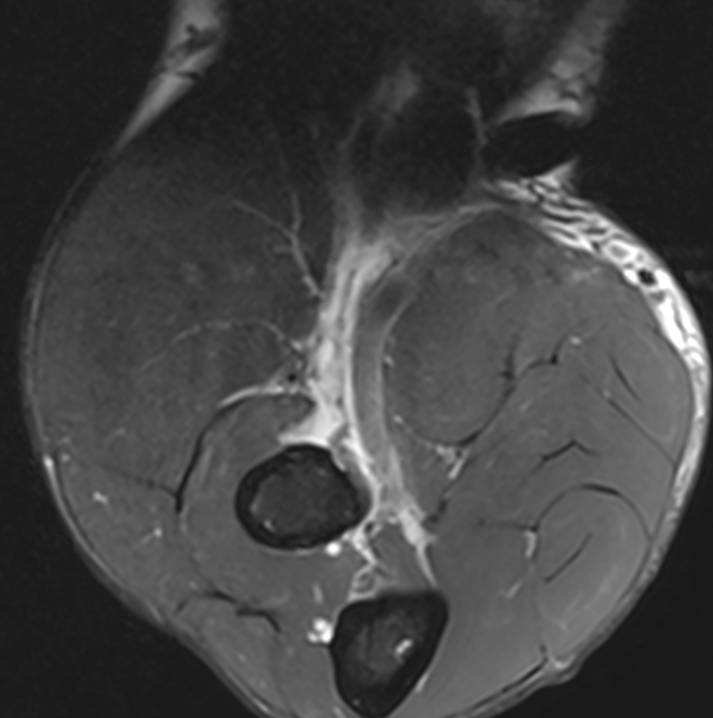

Distal biceps tendon tear and retraction